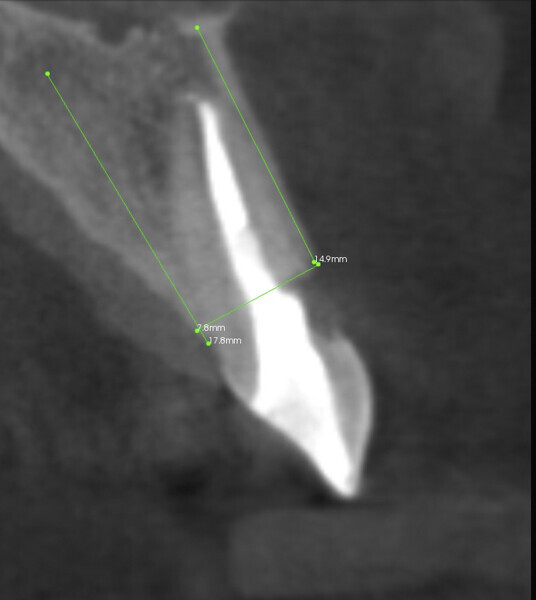

Fig. 2: CBCT scan: the root of the tooth was visibly fractured, and there was clear external resorption of the root from the vestibular side.